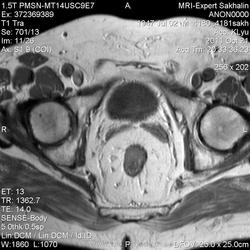

Сегодняшний пациент направлен врачом Онкодиспансера-как обычно без документов, выписок , результатов исследований)))Перенес операцию по удалению опухоли прямой кишки , наложена колостома.

Зато вопросы в направлении:1Протяженность опухоли.2.Depositae in hepar.3Мезоректум.При этом назначил только малый таз....

Прошу помощи!Во-первых, не совсем понятная простата и мочевой пузырь; на некоторых сканах есть признаки тесного прилежания простаты к стенке кишки.В общем-я ничего не понимаю-что удалили!

Признаков распространения опухоли в мезоректум я не вижу (наружный контур кишки четкий, ровный), простата и апоневроз Денонвилье интактны. А в мочевом скорее всего утолщенная межмочеточниковая складка попала в срез .Элевация простаты в мочевой пузырь? Нужны короналы с мочевым пузырем и ПЖ.

Ольга Сергеевна, я завтра у направляющего врача узнаю.Простата гиперплазирована, но прорастания достоверно не вижу.Мезоректум, кажется, тоже интактен.Спасибо за комментарий!